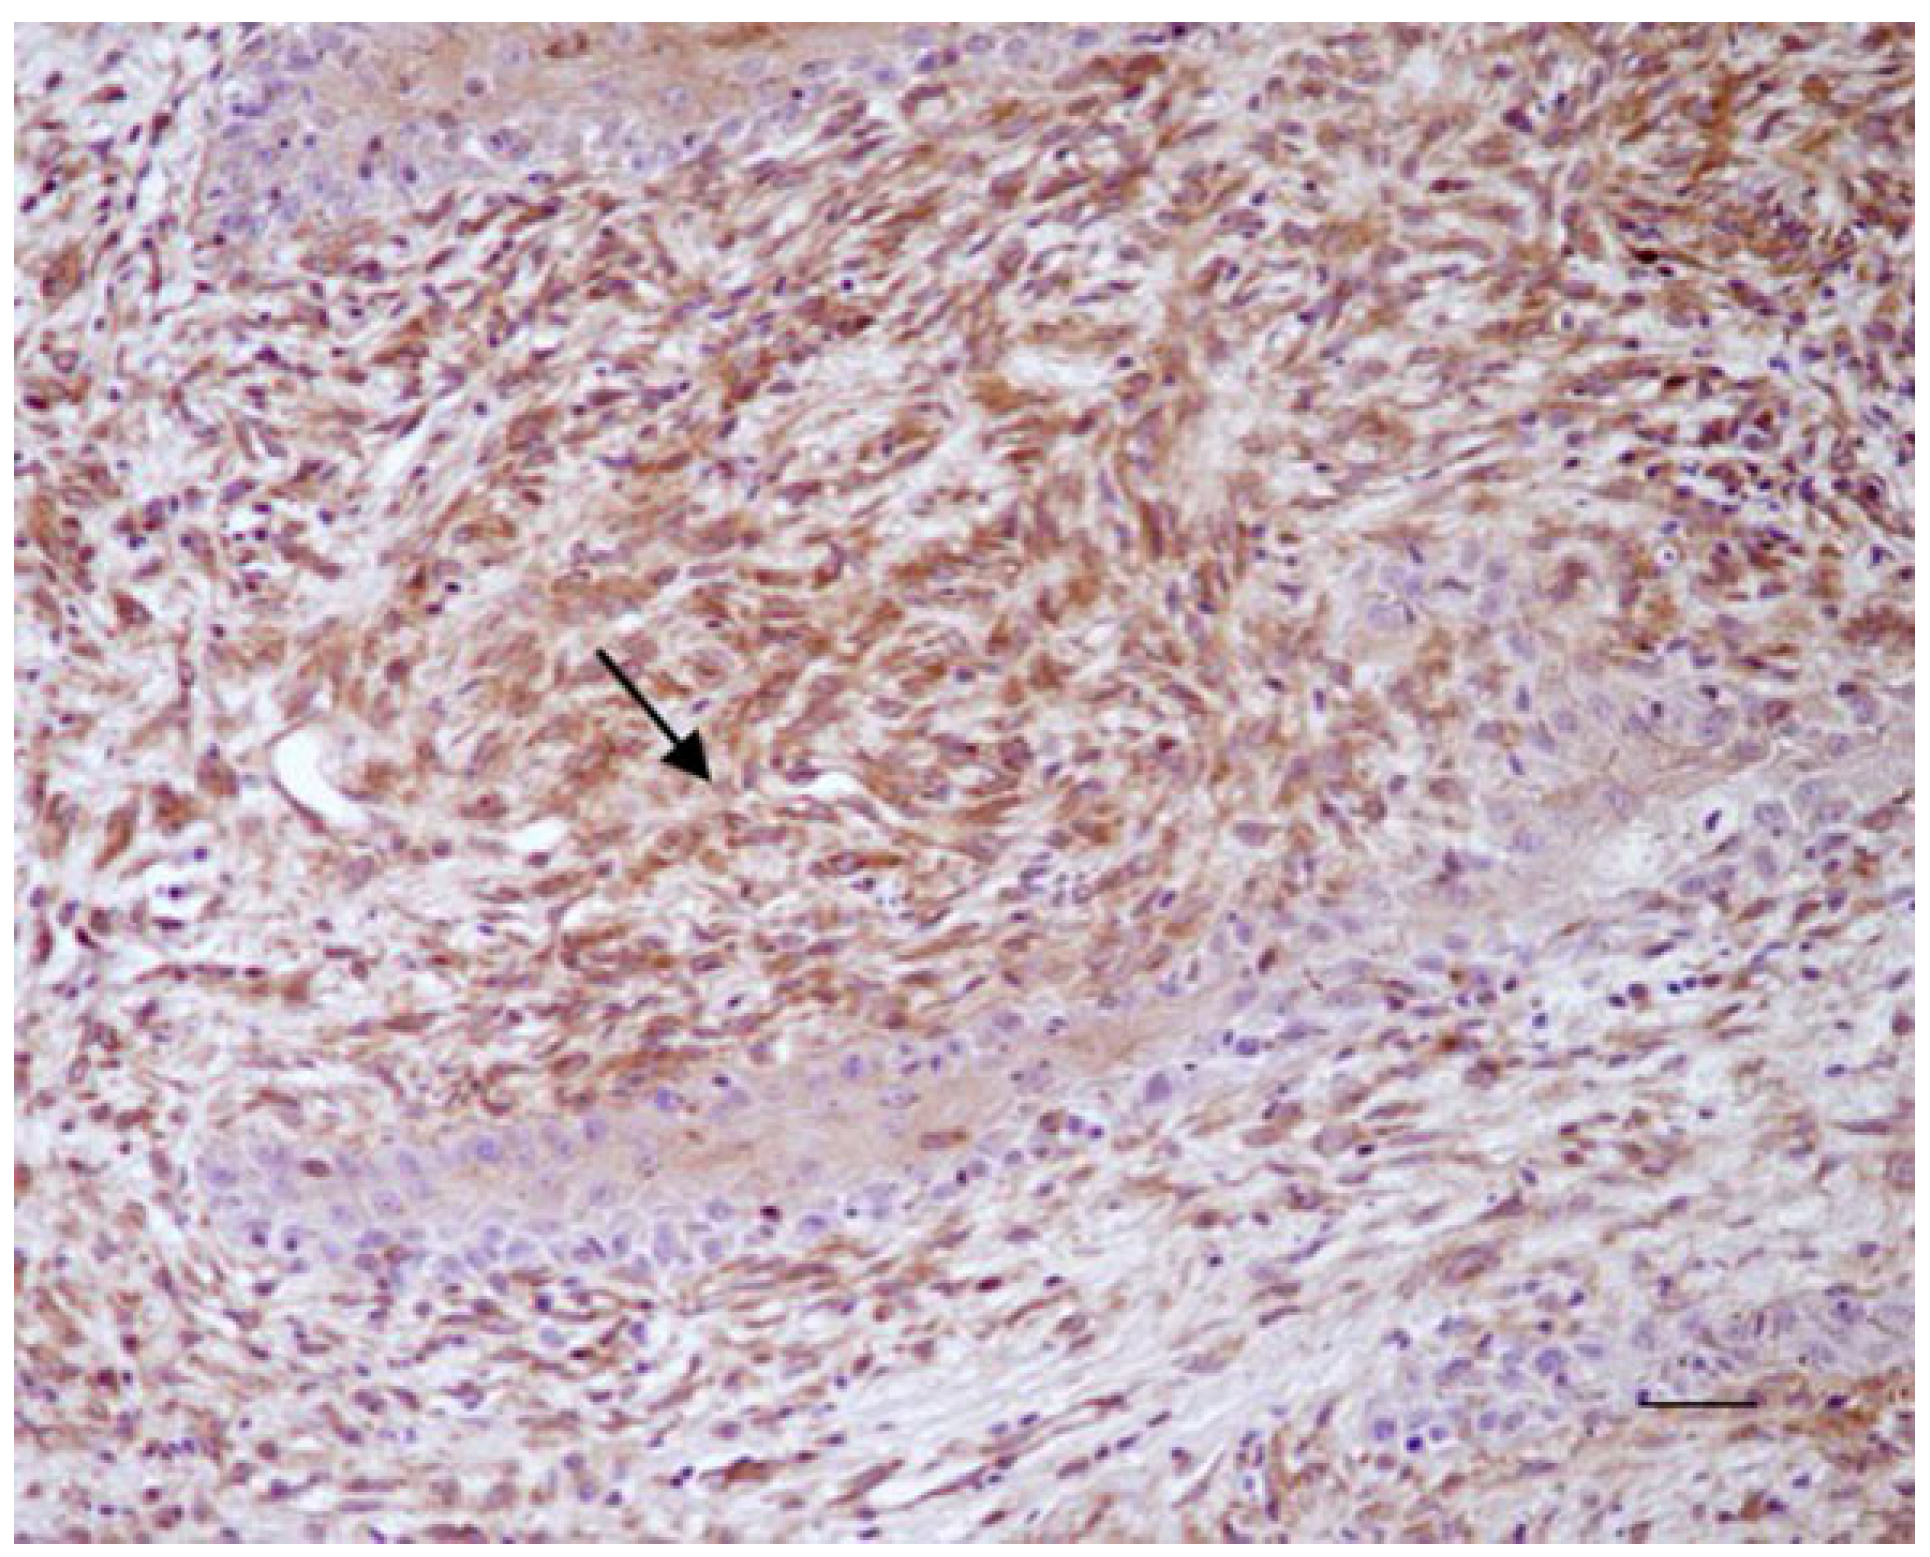

3.1. Histological and Immunohistochemical Results

| Location | Number of Cases | Staining Intensity Score * Beclin 1 | Percentage Positive Score ** Beclin 1 | Staining Intensity Score * LC3 | Percentage Positive Score ** LC3 | Staining Intensity Score * P62 | Percentage Positive Score ** P62 |

|---|---|---|---|---|---|---|---|

| Neck | 2 | ++ | 3 | +/− | 1 | ++ | 3 |

| Limb | 6 | ++ | 3 | +/− | 1 | ++ | 3 |

| 4 | + | 3 | +/− | 1 | ++ | 3 | |

| Abdomen | 4 | ++ | 3 | +/− | 1 | ++ | 3 |

| 2 | + | 3 | + | 2 | ++ | 3 | |

| Pectoral region | 5 | ++ | 3 | + | 2 | ++ | 3 |

| 3 | + | 3 | + | 2 | ++ | 3 | |

| Head | 5 | ++ | 3 | +/− | 1 | ++ | 3 |

| 1 | + | 3 | +/− | 1 | ++ | 3 | |

| (para)-genital region | 3 | ++ | 3 | + | 2 | ++ | 3 |